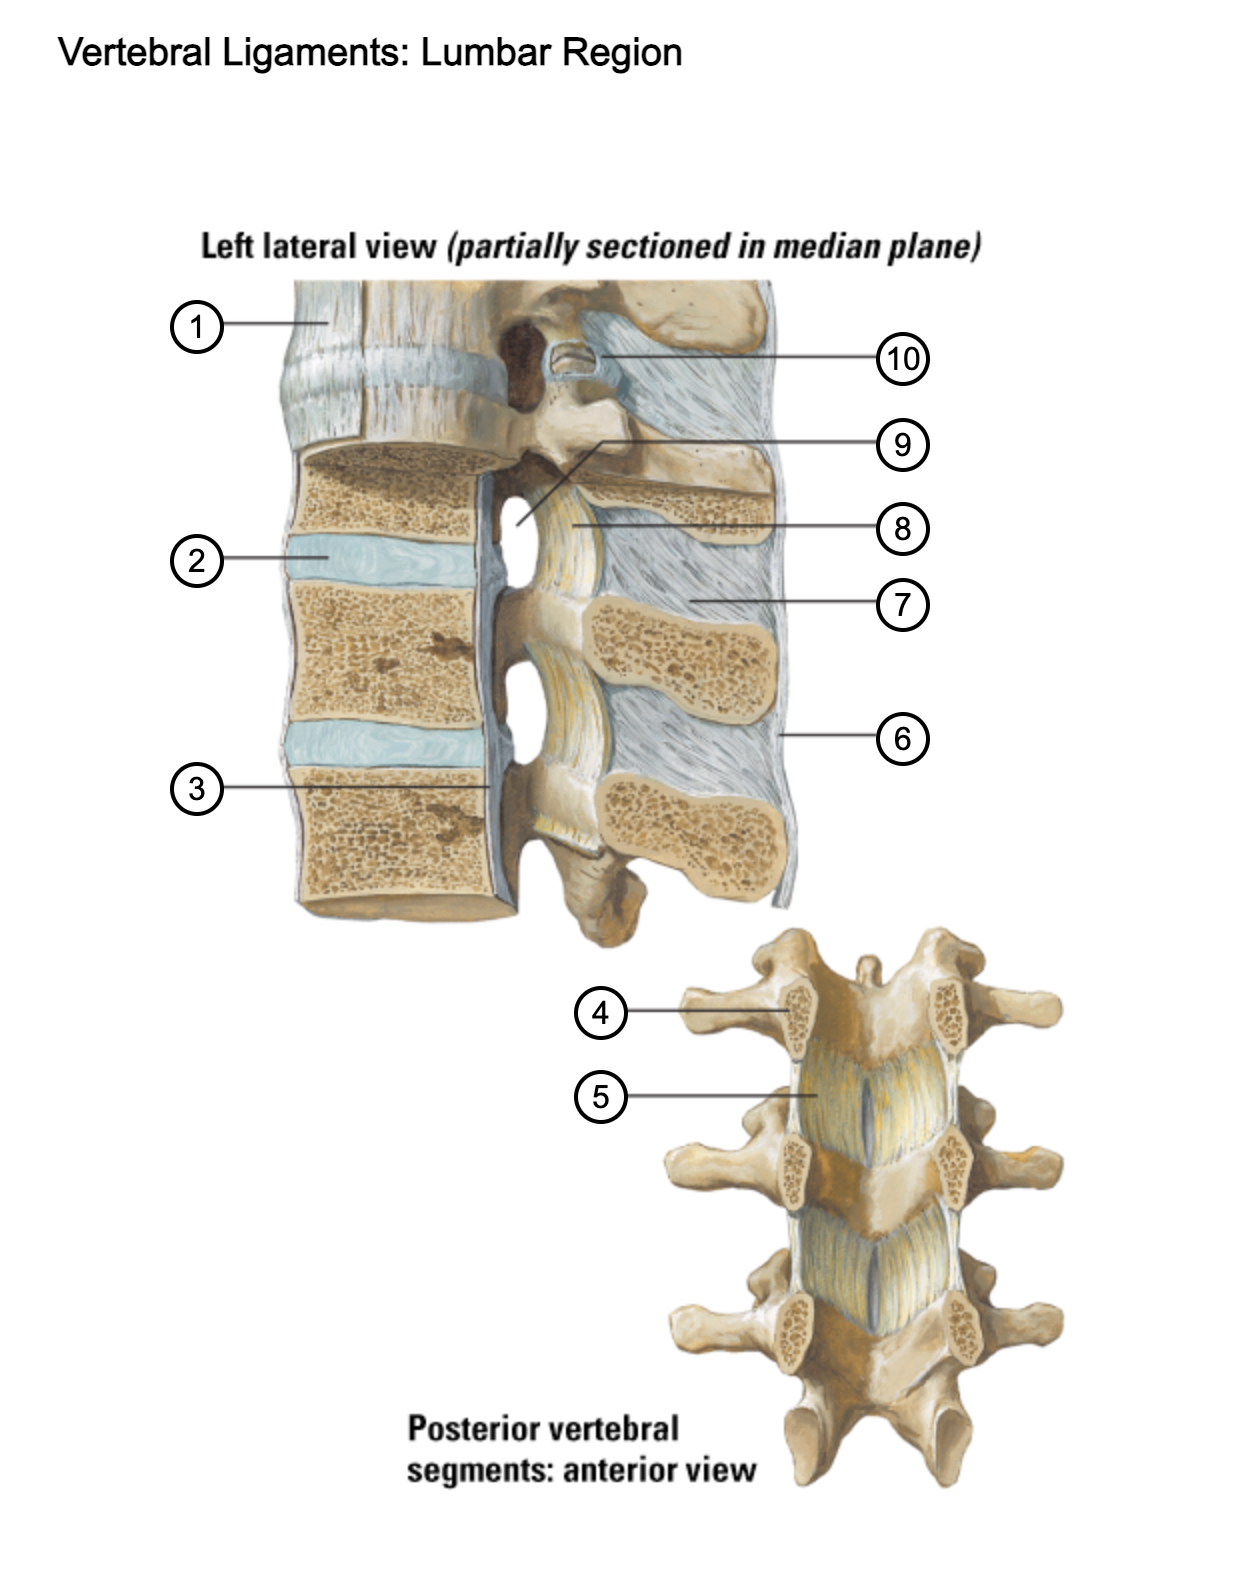

1

anterior longitudinal ligament

2

intervertebral disc

3

posterior longitudinal ligament

4

pedicle (cut surface)

5

ligamentum flavum

6

supraspinous ligament

7

interspinous ligament

8

ligamentum flavum

9

intervertebral foramen

10

capsule of zygapophysial join (partially opened)